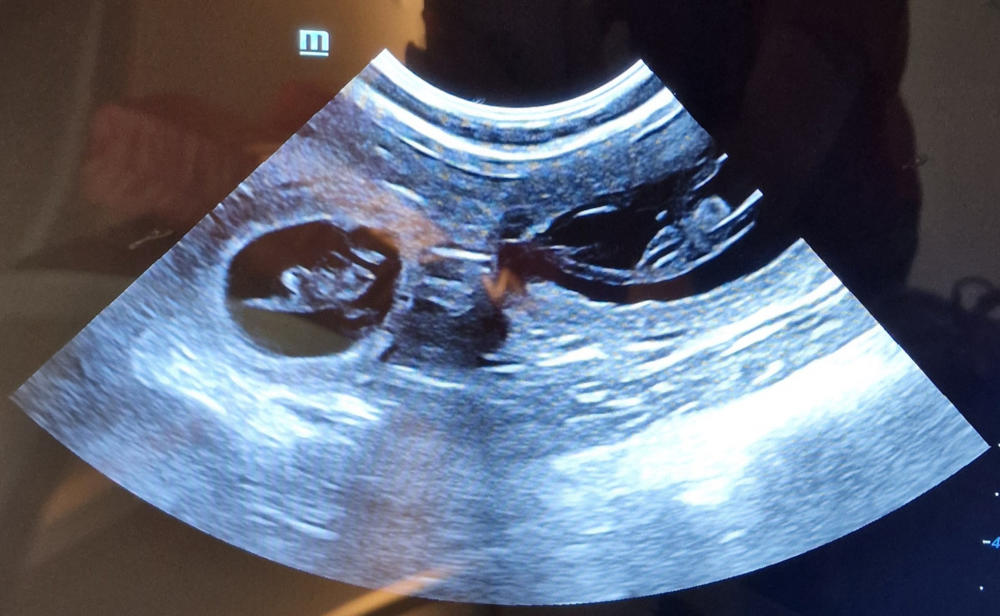

Unsere Mala hatte vor einiger Zeit ein Date mit Olli. (Es muss ja nicht immer Luis sein, hi, hi.) Und siehe da: Der Ultraschall hat es heute bestätigt, dass wieder kleine Bollibabys unter Mala´s Herzchen schlagen. Wir freuen uns sehr.

Unser Frauli war mit Mala „Babys gucken“. Na, könnt ihr sie auch zählen? Smile. In ein paar Tagen ist es soweit. Freu. War nicht wirklich lange ruhig bei uns. Grins. Aber alles andere wäre ja auch langweilig. Hi, hi.